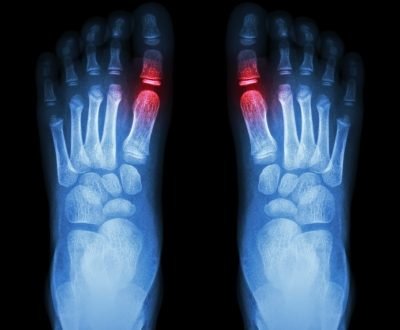

rheumatoid arthritis

pic : freedigitalphotos.net